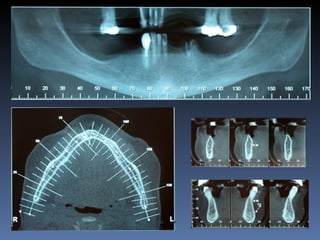

Diagnóstico:Desdentada parcial maxila

Plano de tratamento:      Reabilitação com 6 blocos

“onlay” provenientes de Úmero fresco-congelado

(FFB); reabertura para instalação de 6 implantes

dentários endo-ósseos e reabilitação protética fixa.

22-09-2011

20-04-2012

OPG Pré-op

Mensurações

Zona    Zona    Zona   Zona    Zona     Zona

1.6    1.3     1.1     2.1     2.3      2.6

Stage I       2,0mm   1,5mm 1,5mm 2,9mm 1,5mm         1,5mm

Pré-op (mm)

Stage I     6,5mm     7,0mm 7,1mm 5,2mm 6,7mm         7,0mm

Pós-op (mm)

Aument        4,5mm   5,5mm   5,6mm   2,3mm   5,2mm   5,5mm

o

Espessura

(mm)

Reabert       6,4mm   7,0mm   7,0mm 5,1mm     6,6mm   7,0mm

ura

Stage II

Reabsor       0,1mm   0,0mm   0,1mm   0,1mm   0,1mm   0,0mm

ção

Pós-op 7 dias